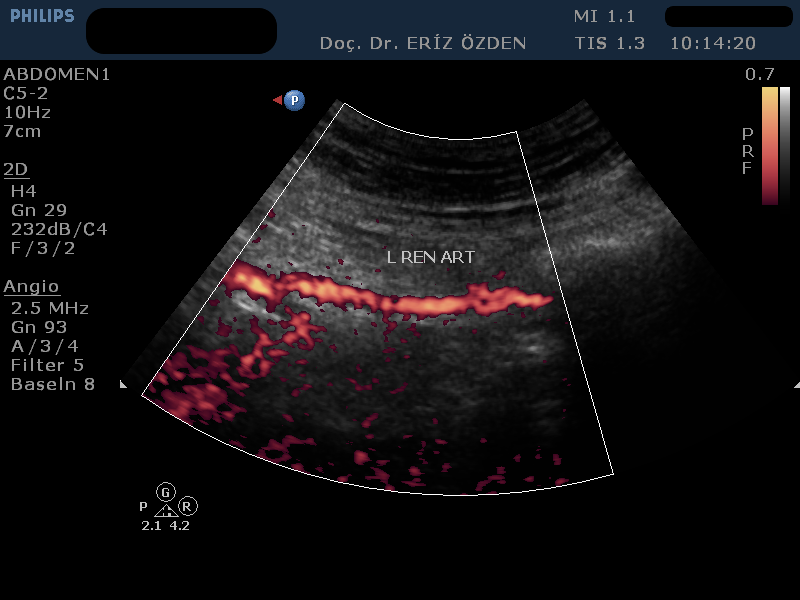

Böbreğe giden atardamarlarda darlık olması durumunda, tansiyon yüksekliği (hipertansiyon) ortaya çıkabilir. Böbrek damarlarının ayrıntılı incelenmesi, darlıkların, tıkanıkların saptanması, böbrek kanlanması hakkında bilgi edinilmesi için Renkli Doppler Ultrason kullanılır. İnceleme sırasında bağırsak gazları görüntüyü bozabileceğinden, hastanın aç olarak gelmesi gereklidir.